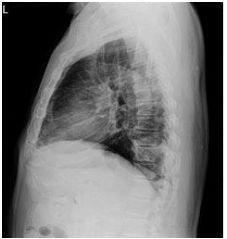

21. 18 years old male. Sudden onset dull chest pain 1 day.